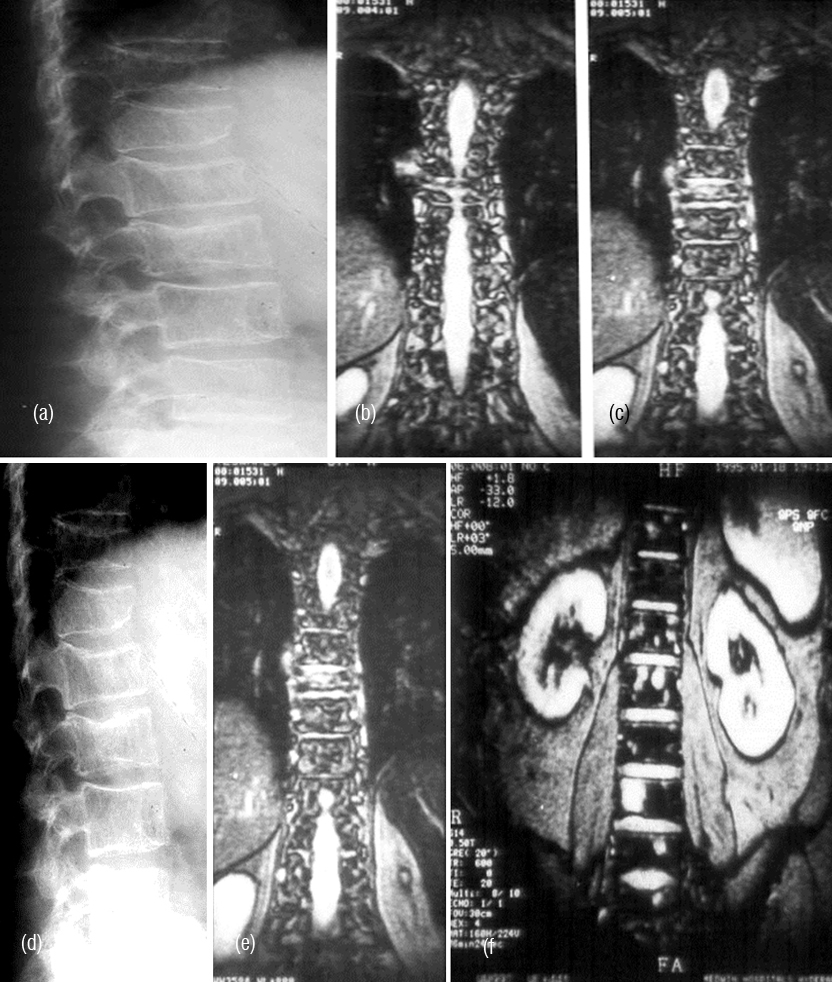

It radiologically shows a spectrum of manifestations. The bones particularly, in axial skeleton may present with multiple compression fractures. In 10-15% of cases, classical punched out lesions of the skull may be noted. In long tubular bones, pathological fractures are common with associated soft tissue swelling. In early skeletal lesions, moth eaten type of appearance is observed without any periosteal reaction (Figure 6ab). MRI is more sensitive to depict bone marrow lesions, whereas radionuclide scintigraphy with technetium 99 compounds is not that sensitive (Figure 7abcdef). The radiological appearances are listed in Table 3.

Figure 7: (a,b,c) Multiple myeloma with osteopenia and early collapse of vertebral bodies BC MRI of the same patient. (d) plain films, (e, f) MRI.